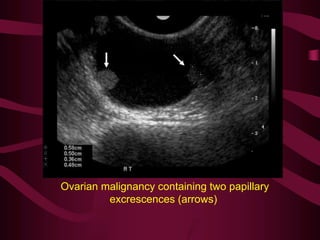

Ovarian malignancy containing two papillary

excrescences (arrows)